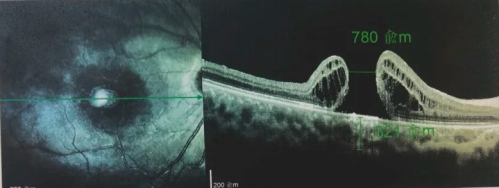

由于自身患有頸椎病,每次術(shù)后長(zhǎng)期的趴睡都讓他痛苦不堪。為了尋求更好的治療,吳爺爺來到廈門大學(xué)附屬廈門眼科中心,找到了眼外傷及眼底病2科的李海波博士后。此時(shí),吳爺爺右眼的黃斑裂孔已經(jīng)持續(xù)擴(kuò)大到780μm,演變?yōu)殡y治性的大裂孔。

經(jīng)過完善的術(shù)前檢查和專業(yè)評(píng)估后,李海波博士后決定采用創(chuàng)新的治療方案——SPOT 技術(shù)輔助下遠(yuǎn)周邊移植自體內(nèi)界膜覆蓋,為他進(jìn)行治療,手術(shù)在20分鐘內(nèi)順利完成。

最讓吳爺爺難以置信的是:術(shù)后只需保持平躺24小時(shí)!第二天復(fù)查時(shí),眼底鏡及OCT檢查清晰顯示——那個(gè)折磨了他大半年的大裂孔,竟然閉合了!且吳爺爺?shù)挠已垡暳τ辛嗣黠@的改善,術(shù)后3天已經(jīng)可以看到 0.15。